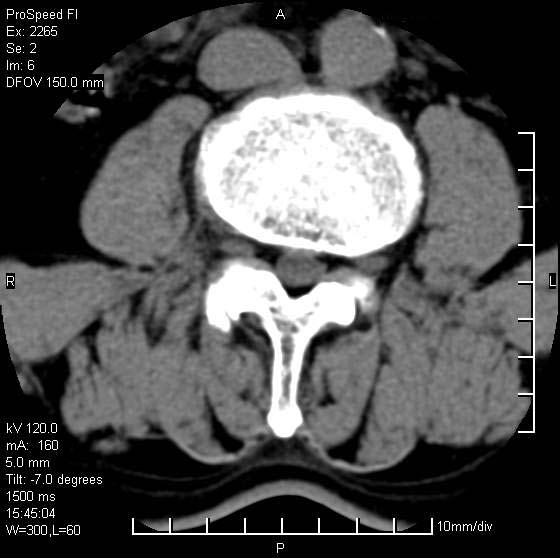

以下是引用qiushi在2007-8-22 17:26:00的发言:[br]没骨窗![br] 1、 l5~s1间盘膨出伴轻度突出(中央型)、变性。[br] 2、l4~5间盘膨出伴突出(右侧远外侧型)。[br] 3、l3~4间盘膨出。[br] 4、腰椎退行性变。[br]

以下是引用随缘的人在2007-8-22 20:56:00的发言:[br]腰椎退行性变:1。l4/5,l5/s1膨出[br] 2。l5/s1间盘退行性变 [br] 3。腰椎骨质增生

以下是引用liaizhi在2007-8-22 22:13:00的发言:[br]1,l4-5锥间盘膨出,2,l5-s1椎间盘膨出并退变(椎间盘呈真空征);3,血管瘤(椎体骨小梁稀疏粗大)?